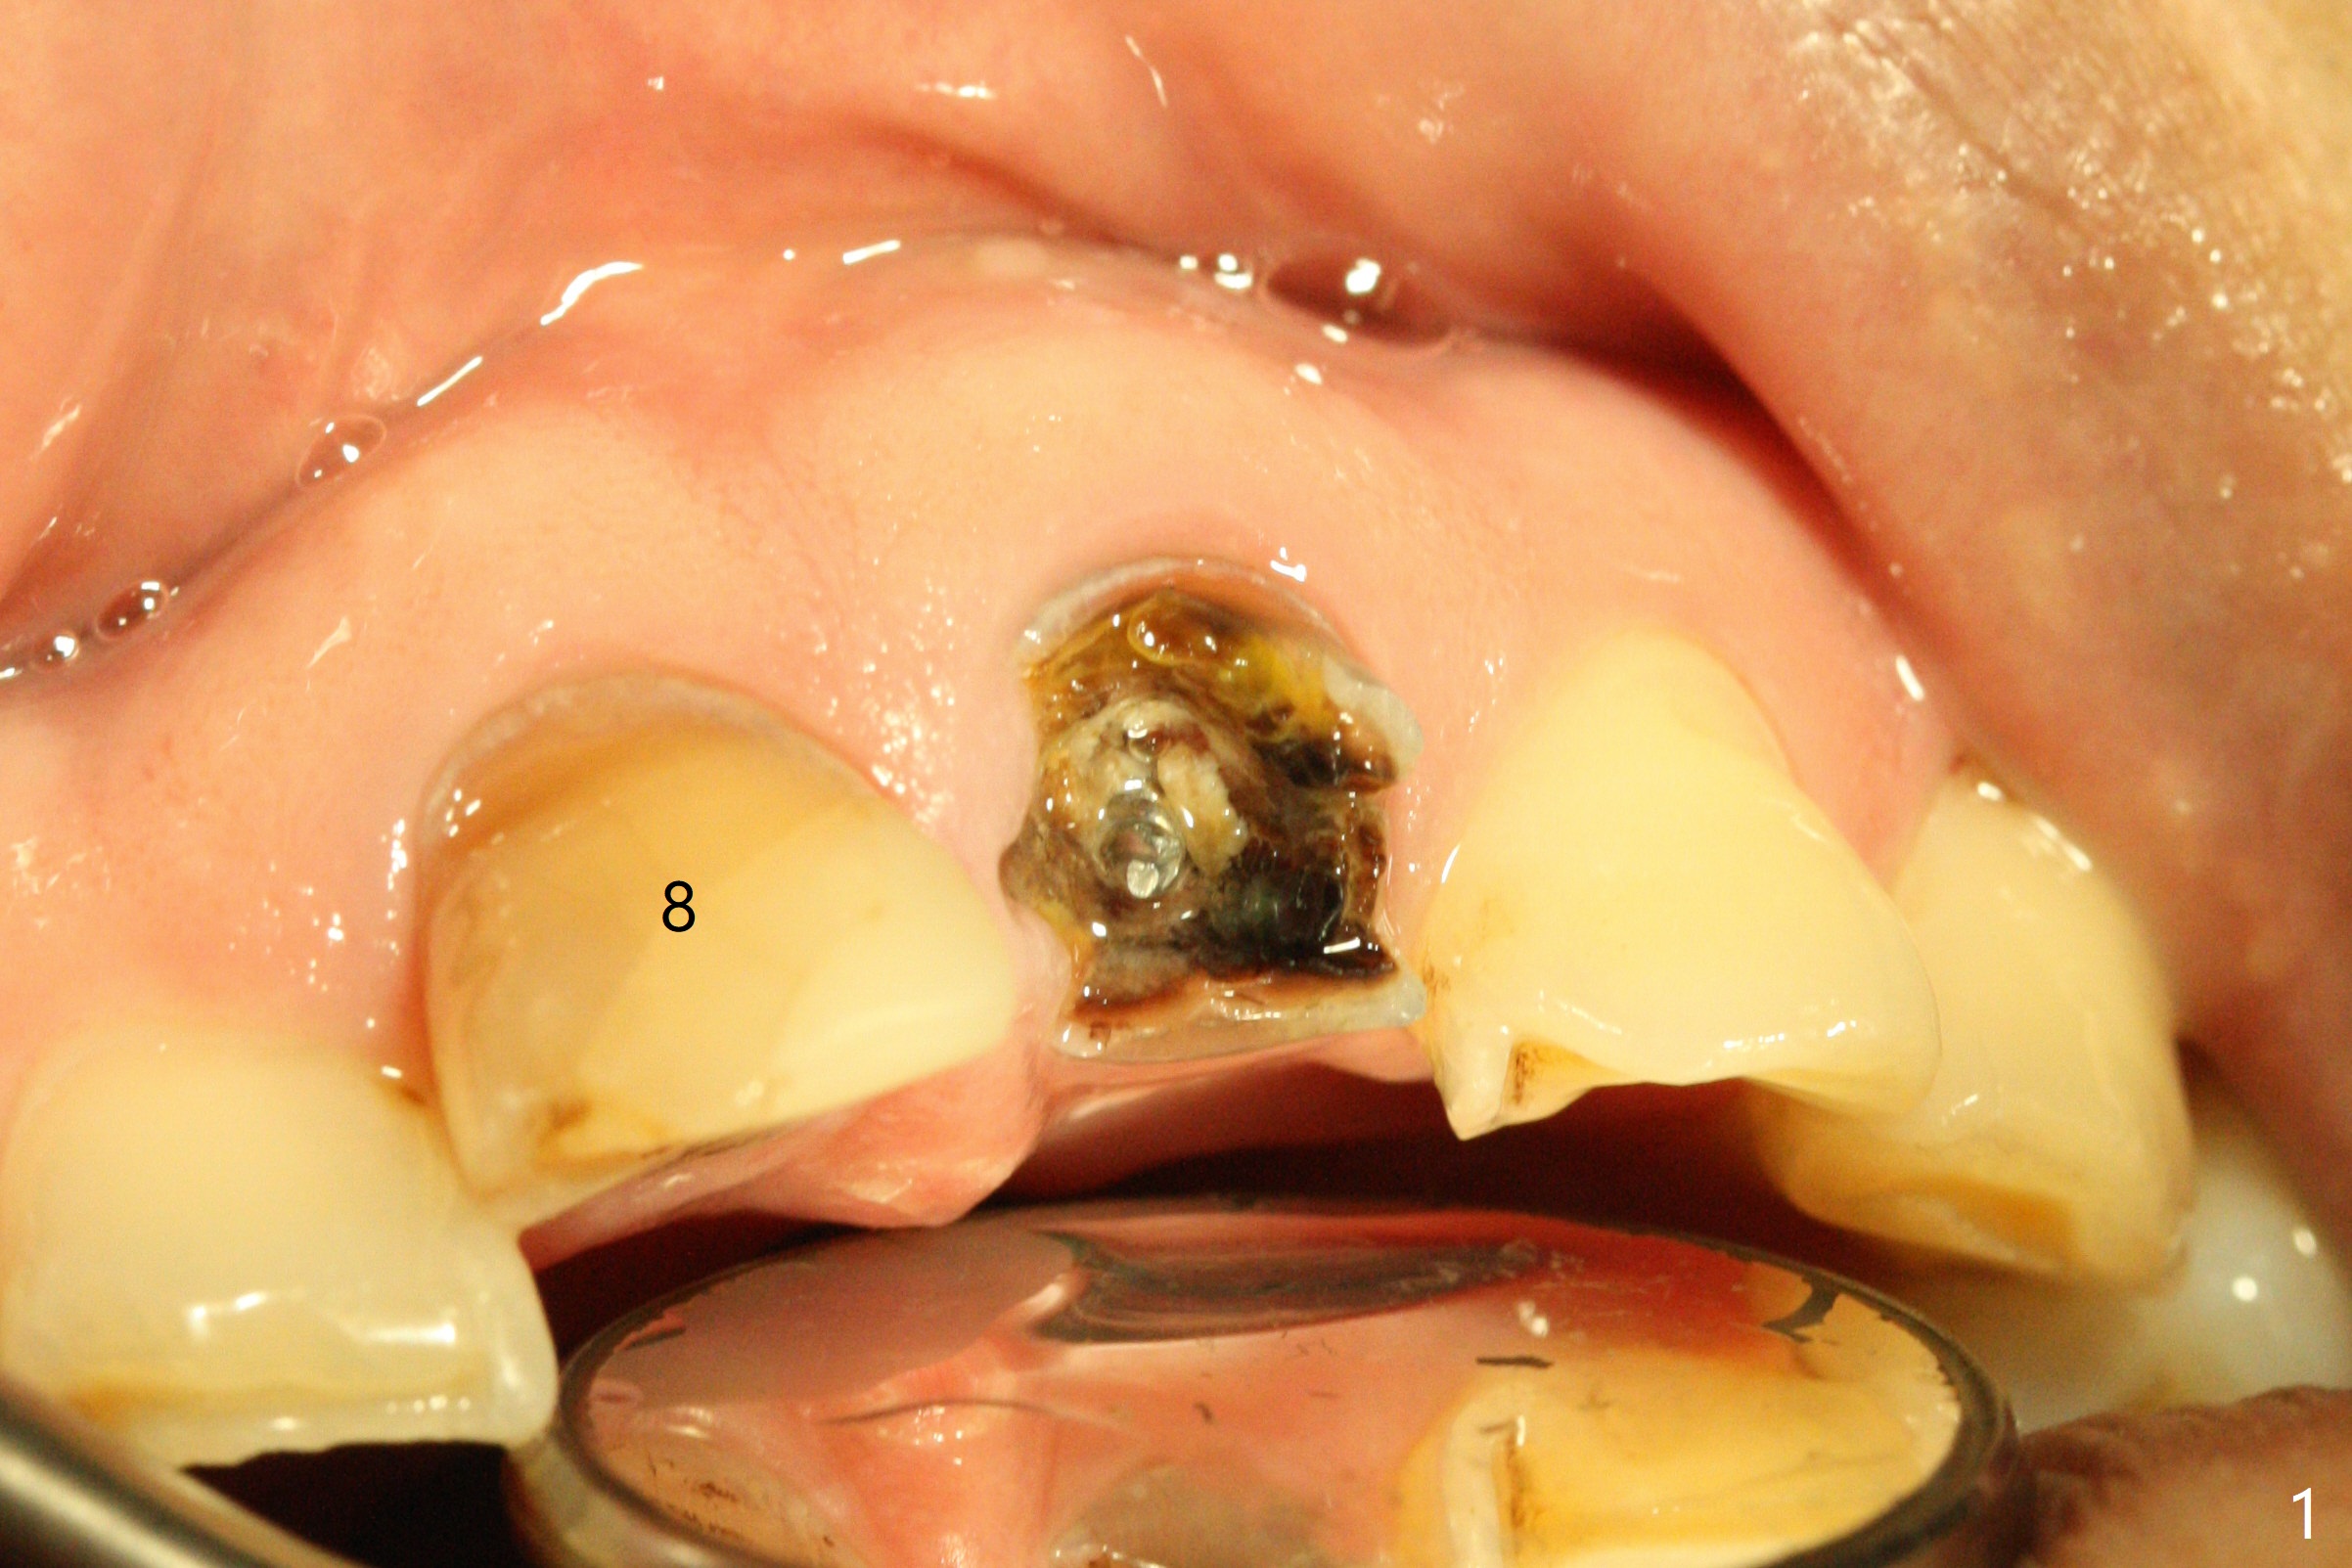

A 57-year-old man has history of fracturing post-RCT molar and difficulty in orthodontic intrusion. Now the tooth #9 fractures subgingival (Fig.1) with deep bite and heavy wear (Fig.2). A long implant will be placed to handle heavy occlusion and match the root length of the neighboring tooth (Fig.3 #10).